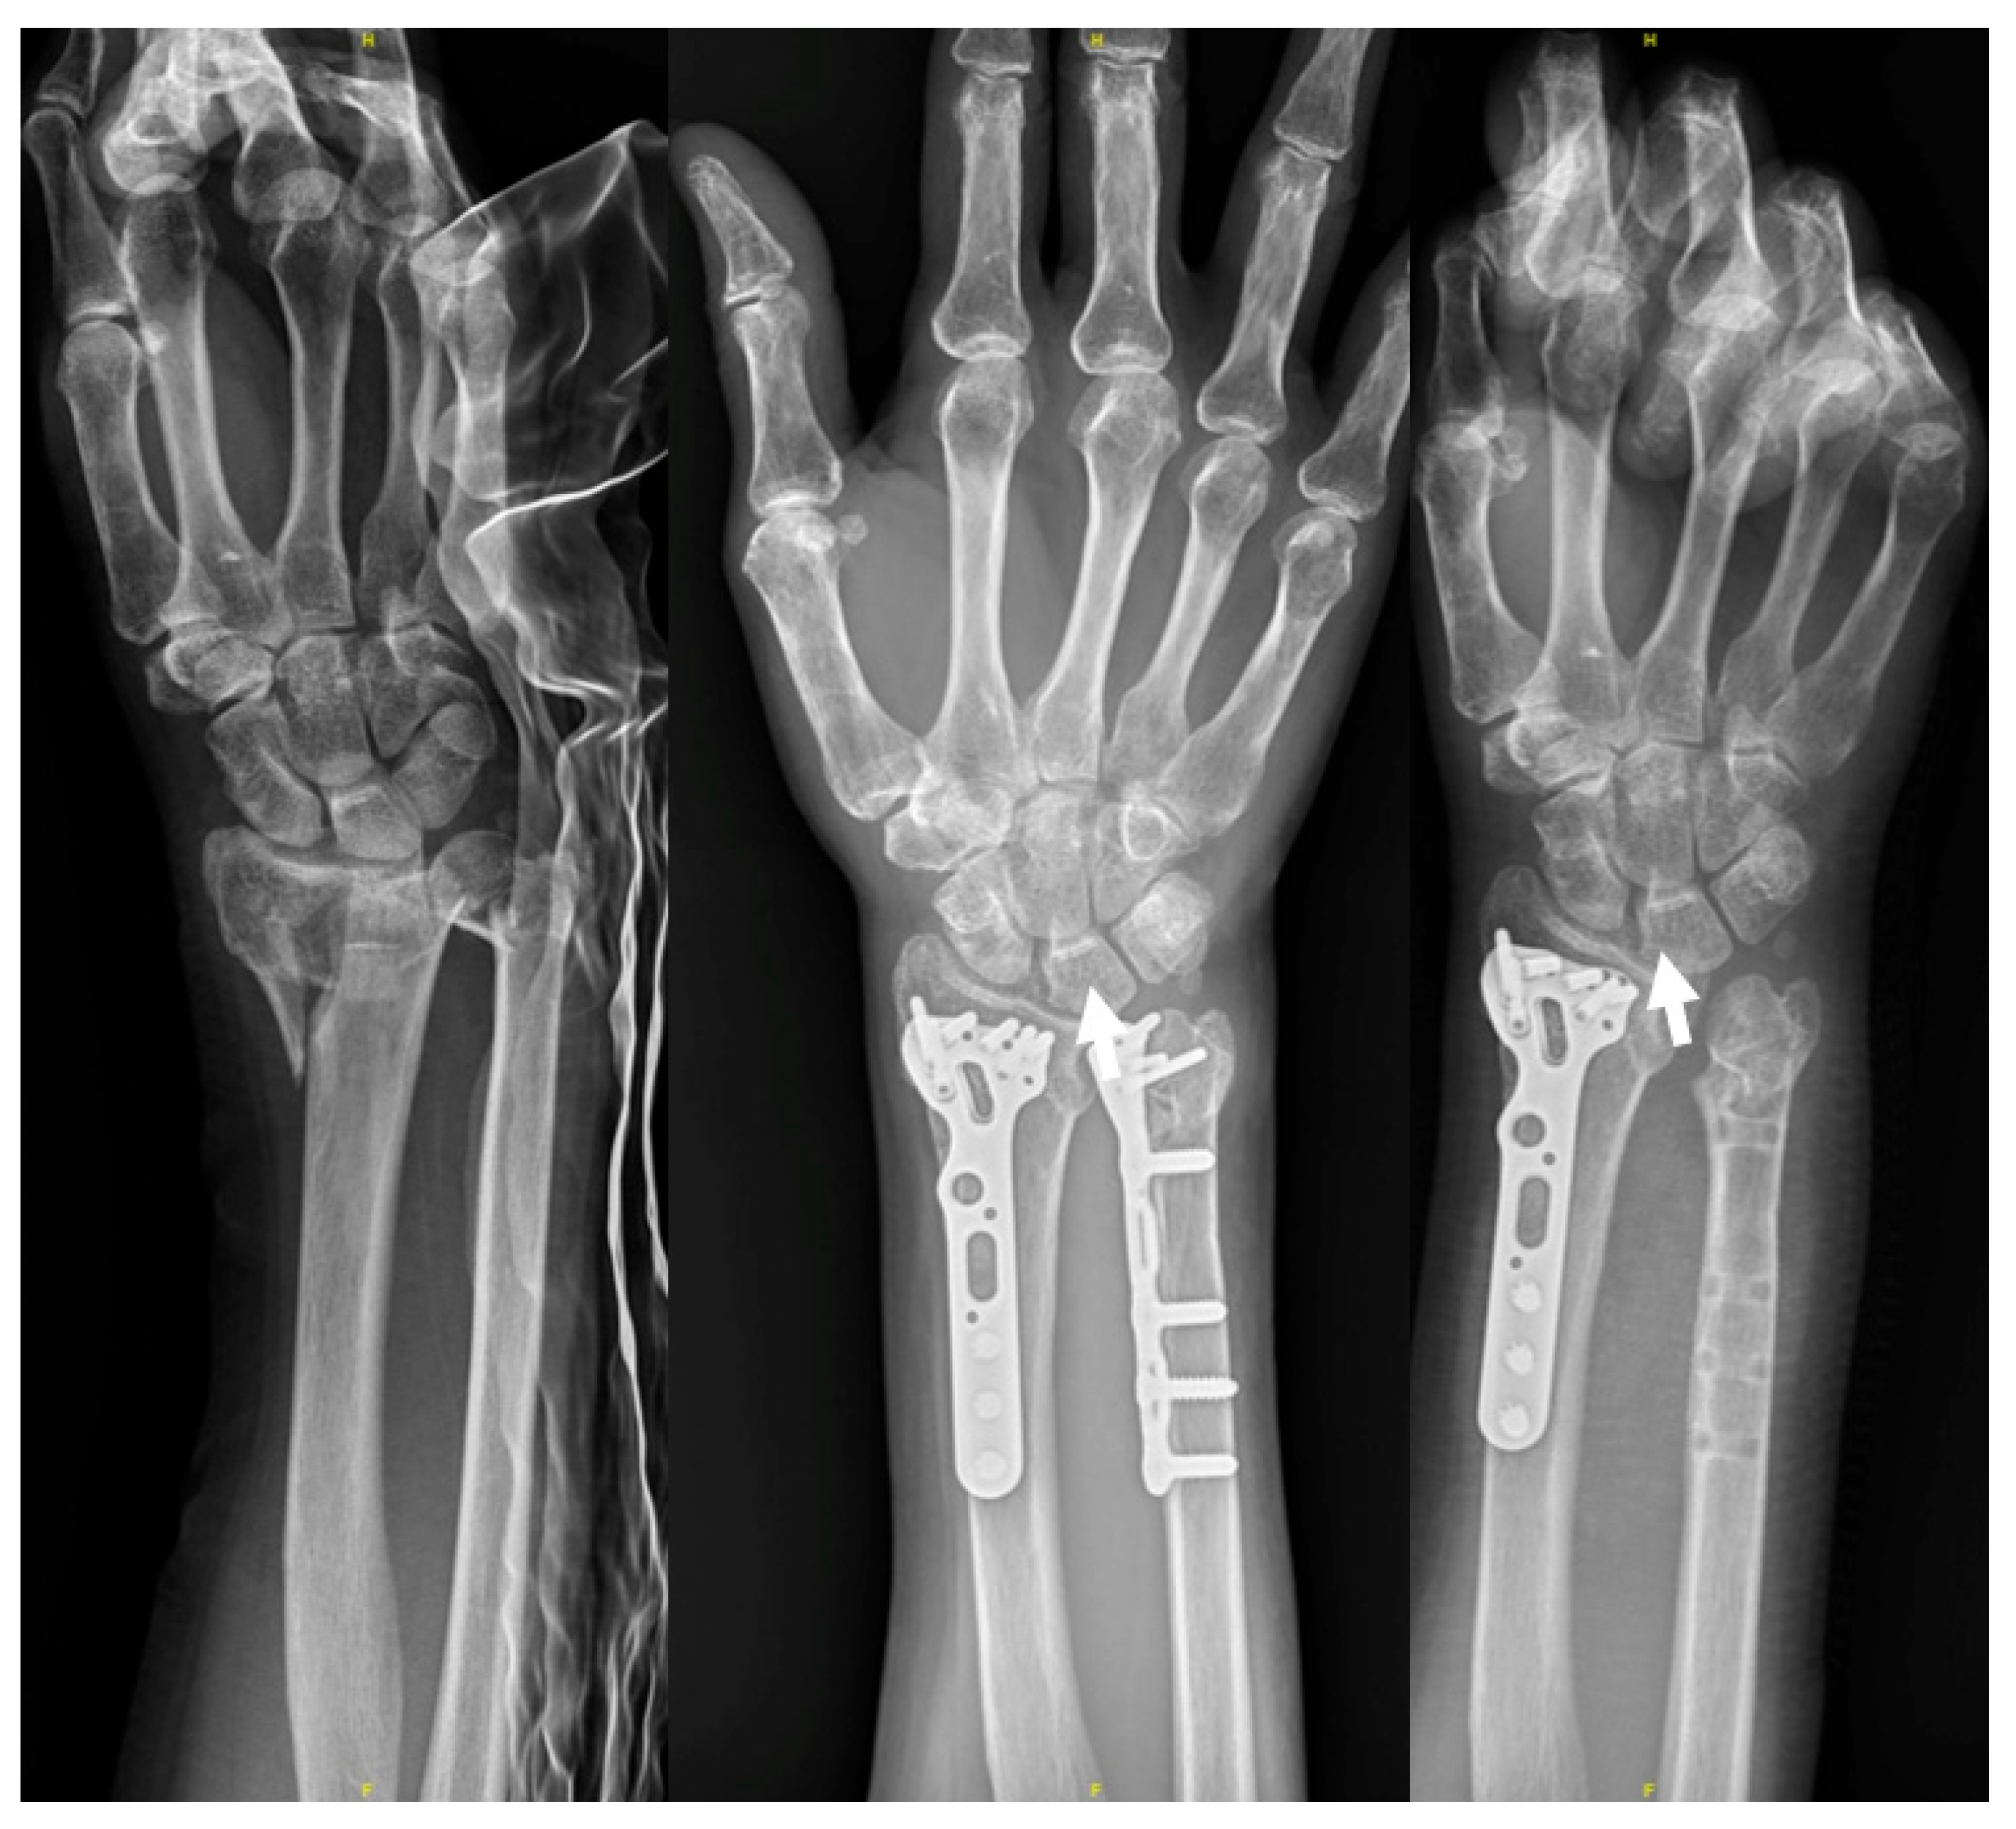

Figure 2.

(A) A sixty-seven-year-old woman sustained a distal forearm fracture. She underwent ORIF to both bones via the modified dual channel approach. The figure shows anteroposterior/lateral view at initial and postoperative day 1. (B) Ensure the locking plate placement on the ulna does not extend beyond the radius sigmoid notch to avoid impingement. The three intraoperative fluoroscopic images, respectively, represent the AP view, PA view, and lateral view, which may help us identify the plate positioning and avoid screw intra-articular penetration.